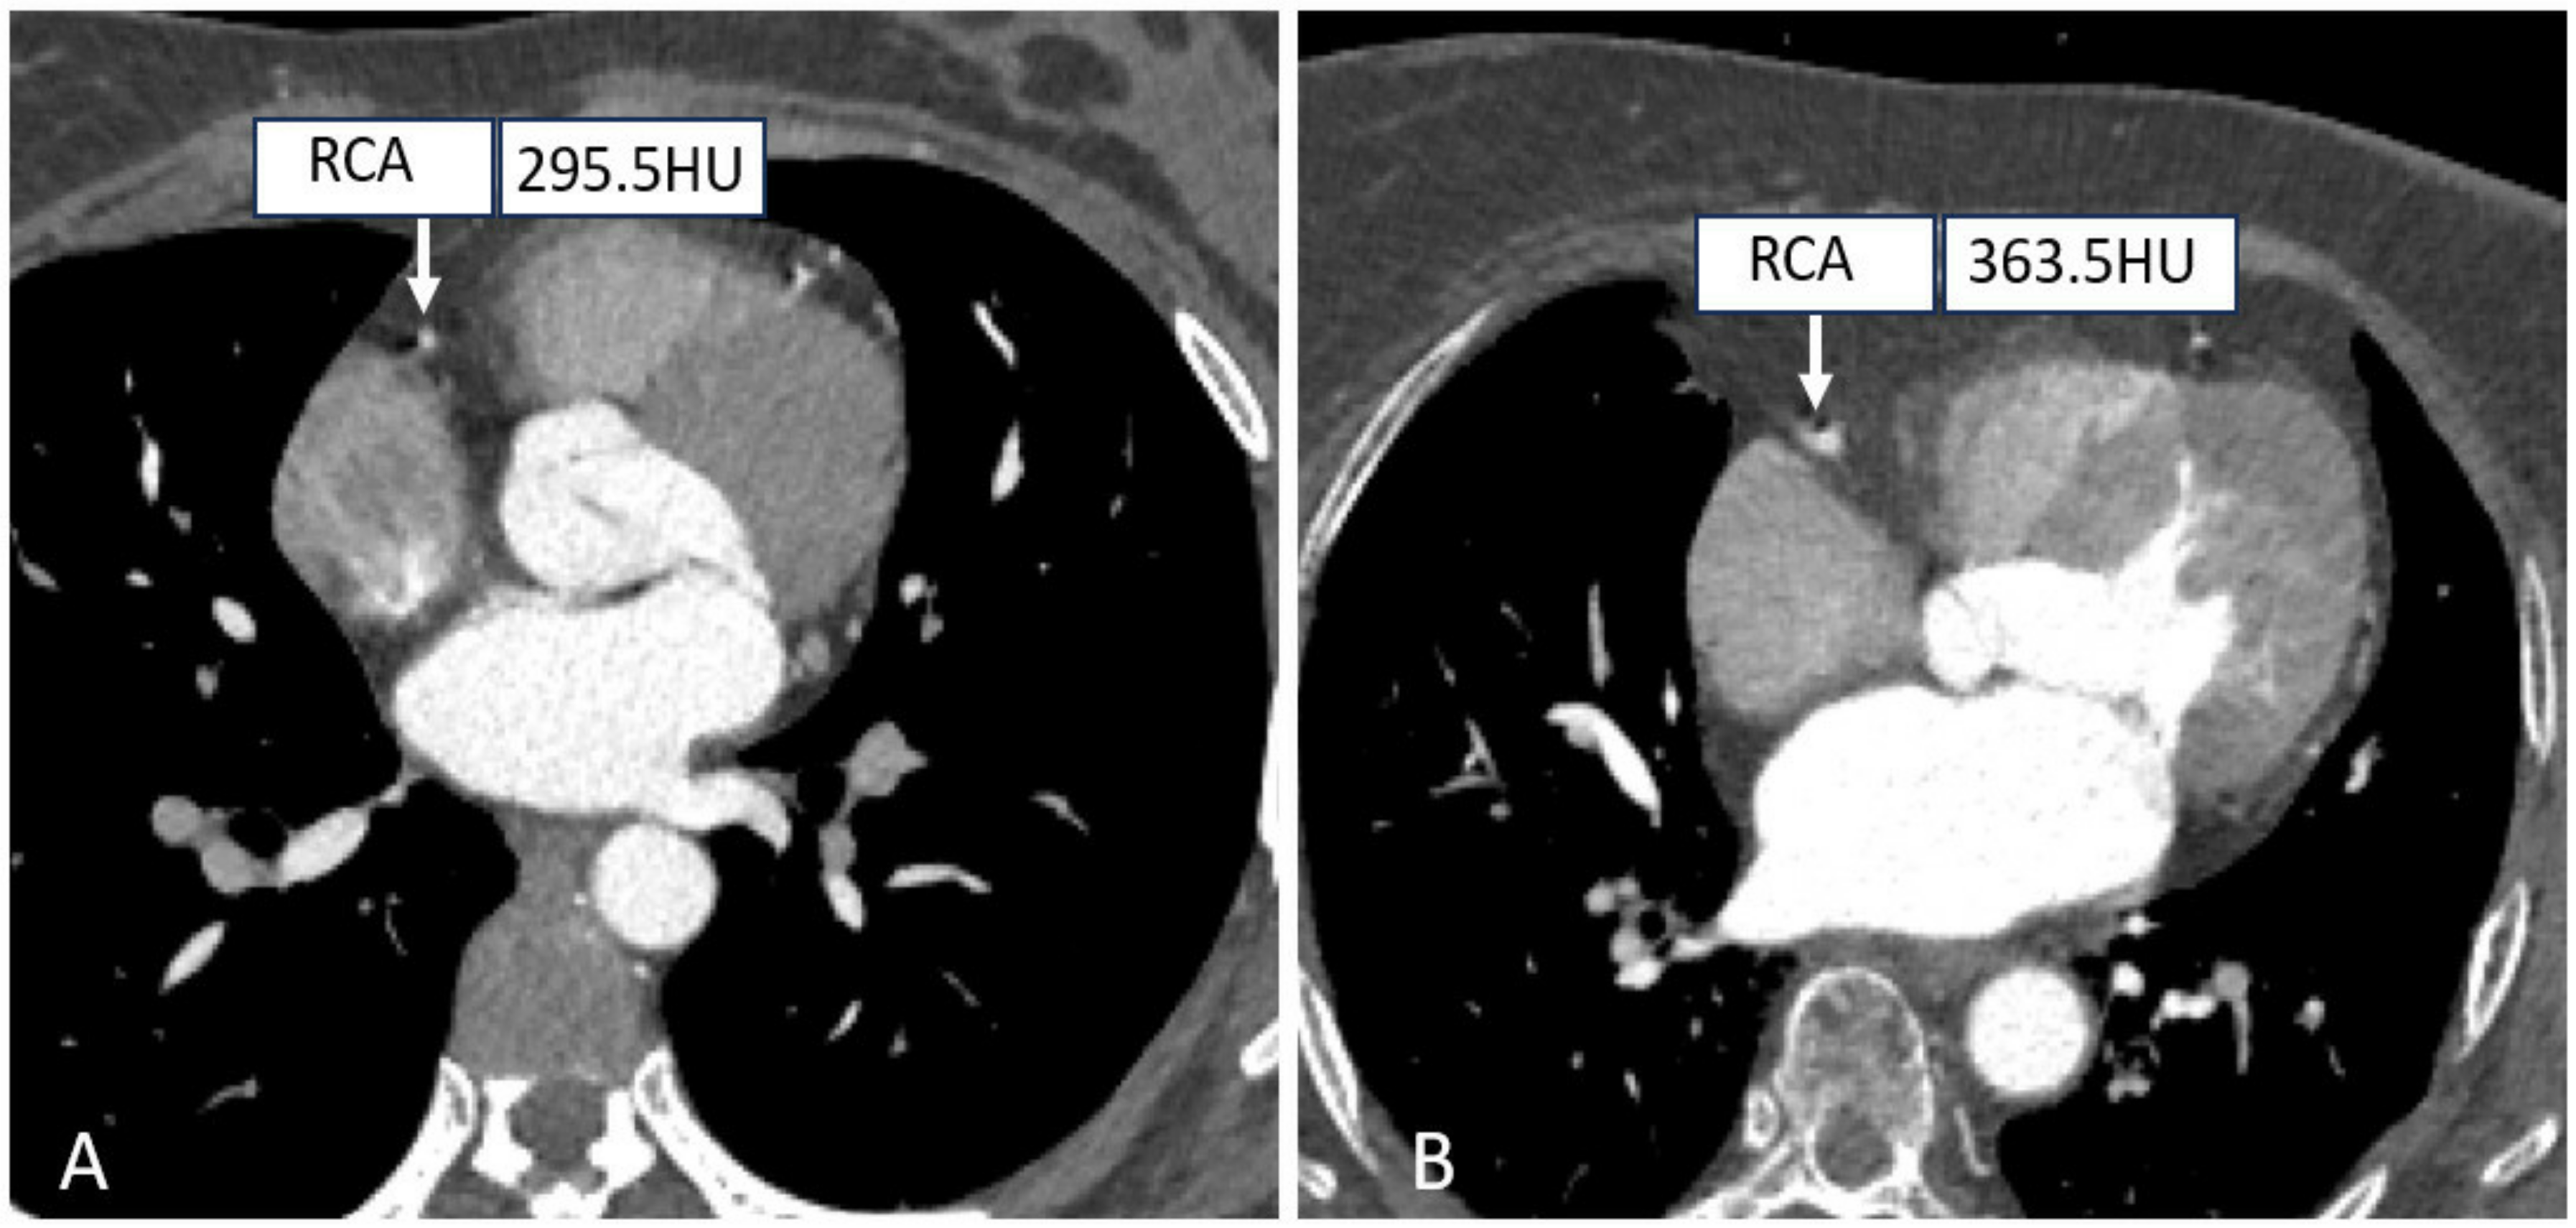

- Wang, X.; Yang, F.; Zhu, Y.; Xiao, Z.; Cui, S. Feasibility Research of Low Concentration Contrast Agent Iodixanol (270 mg I/mL) Combined with the Lower Tube Voltage in Coronary CTA with 640-slice Volumetric CT. J. Hebei North Univ. (Nat. Sci. Ed.) 2018, 83, e92–e99. [Google Scholar]